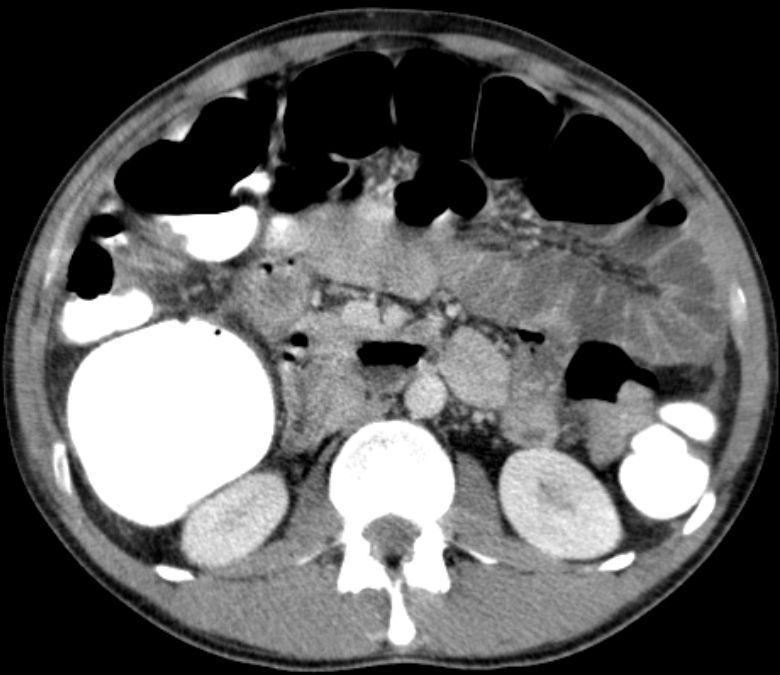

| Beispiele bildgebender Diagnostik von primären Colonkarzinomen | Zökum |

Colon ascendens |

Colon descendens | |